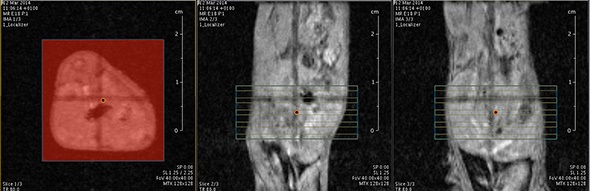

I think that also the low-field, let’s say the low/intermediate field to work at the 1 Tesla for instance as in the case of this beautiful Icon system, this gave us unique possibilities. Anytime we use a gadolinium-based agent or more in general a paramagnetic basic agent the best field is the 1 Tesla.

So, we can show that there is a real advantage of working at 1 Tesla in comparison to for instance 7 or 9 Tesla when one is using a relaxation enhancer to target a specific epitope in the region of interest.